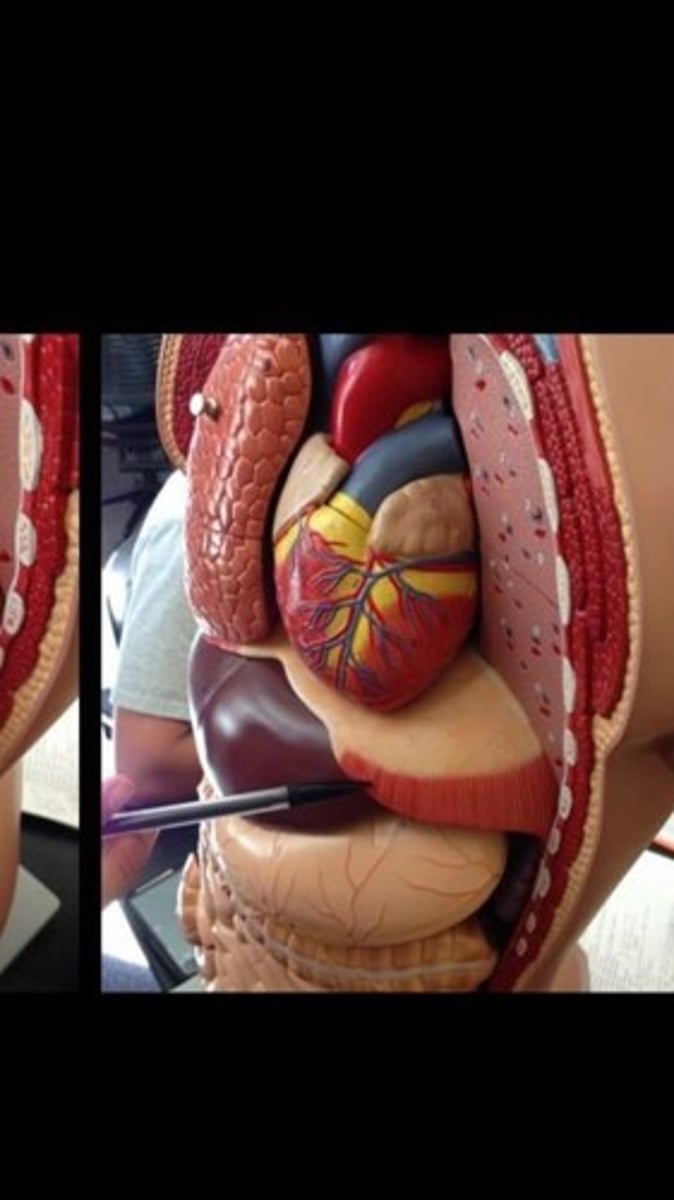

Skeletal muscle terms and structure

114 Terms

Diaphragm